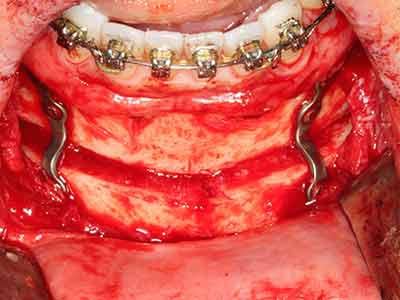

En la extracción de bloques óseos la piezocirugía también presenta ventajas adicionales: Además de la alta precisión en la osteotomía que ya se ha descrito antes, se ha comprobado que el uso de los delgados insertos de sierra resulta especialmente cuidadosas con el hueso. Frente a esto, sobre todo cuando se usan las fresas de Lindemann, cabe esperar pérdidas en la extracción significativamente más altas debido al mayor grosor de la parte frontal del cabezal (Lakshmiganthan, Gokulanathan et al. 2012). La separación basal que se necesita en particular en los injertos de bloque extraídos de forma retromolar se ve facilitada mediante sierras perpendiculares especialmente previstas a tal fin, lo que permite considerar que la cirugía piezoeléctrica es un procedimiento preciso y seguro para la obtención de bloques de hueso en el área retromolar (Happe 2007) (fig. 1-12).

Aplicación: Partición ósea / Cortical Split

El tejido óseo no solo tiene un contenido puramente mineral, sino que también presenta una importante proporción de fibras de colágeno. Esto no solo garantiza una buena resistencia a la presión, sino también una cierta flexibilidad, que puede aprovecharse para la realización de aumentos. En la plastia de expansión clásica a efectos de una partición ósea, la cresta maxilar atrofiada se divide en su eje longitudinal y, tras alcanzar una profundidad de osteotomía suficiente, se extiende con cuidado (fig. 13-16), en un caso ideal sin desperiostizar de forma visible el maxilar (Brugnami, Caiazzo et al. 2014, Stricker, Fleiner et al. 2014). Los sistemas de tornillos y placas con distancia de expansión creciente han demostrado su eficacia para distanciar entre sí las dos tablas óseas por debajo del umbral de rotura. Por regla general, se requieren anchuras de hueso residual de al menos 3 a 4 mm (Chiapasco, Zaniboni et al. 2006) para garantizar una flexibilidad y una cobertura ósea suficientes de los implantes que van a incorporarse. En caso necesario, una osteotomía de descarga vertical unilateral o bilateral puede mejorar la flexibilidad. Como alternativa a la técnica clásica se ha descrito una combinación con otras técnicas de aumento, sobre todo en la parte bucal.

Con el uso de sierras piezoeléctricas la división se efectúa de forma especialmente cuidadosa y sin pérdidas importantes de las dimensiones, por lo que no se han encontrado diferencias significativas entre los implantes realizados en el maxilar dividido y en la cresta alveolar no deficitaria (Chiapasco, Zaniboni et al. 2006, Danza, Guidi et al. 2009). No obstante, precisamente en la partición profunda y limitada de forma local, es preciso asegurarse de que exista una adecuada irrigación por agua para evitar que se produzcan sobrecargas térmicas en las áreas de osteotomía apical.